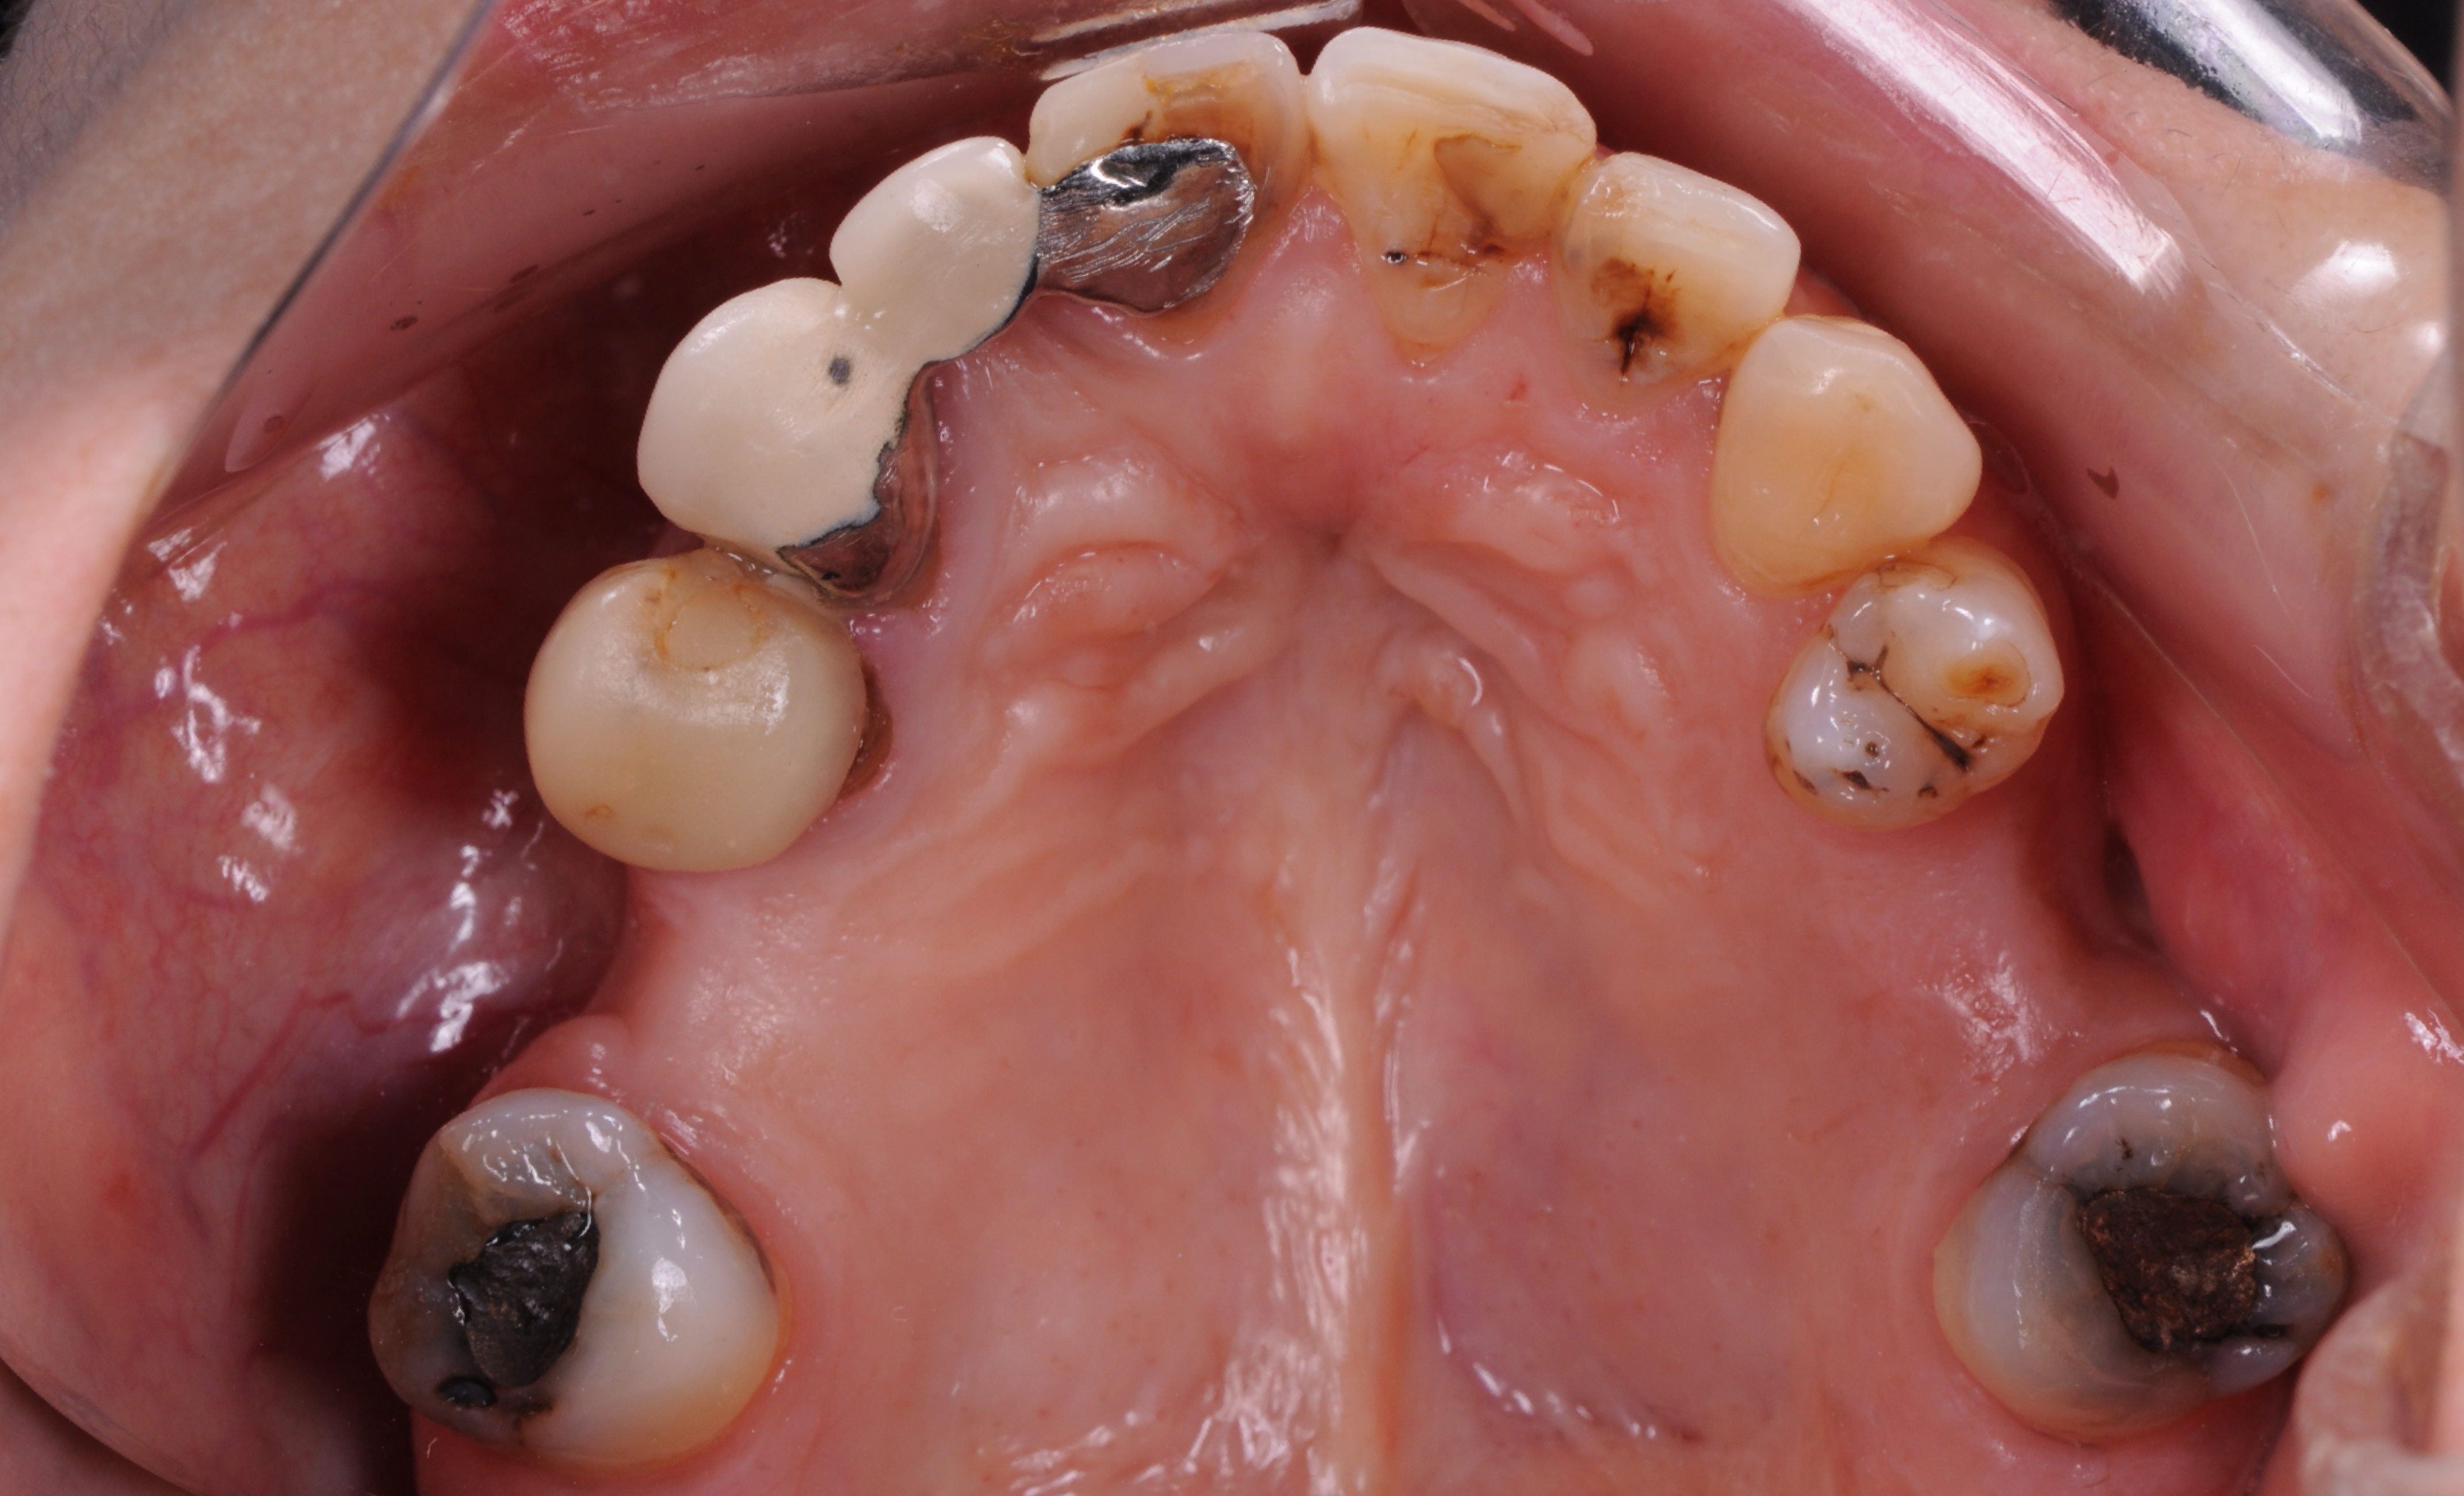

Estado inicial do dentes.